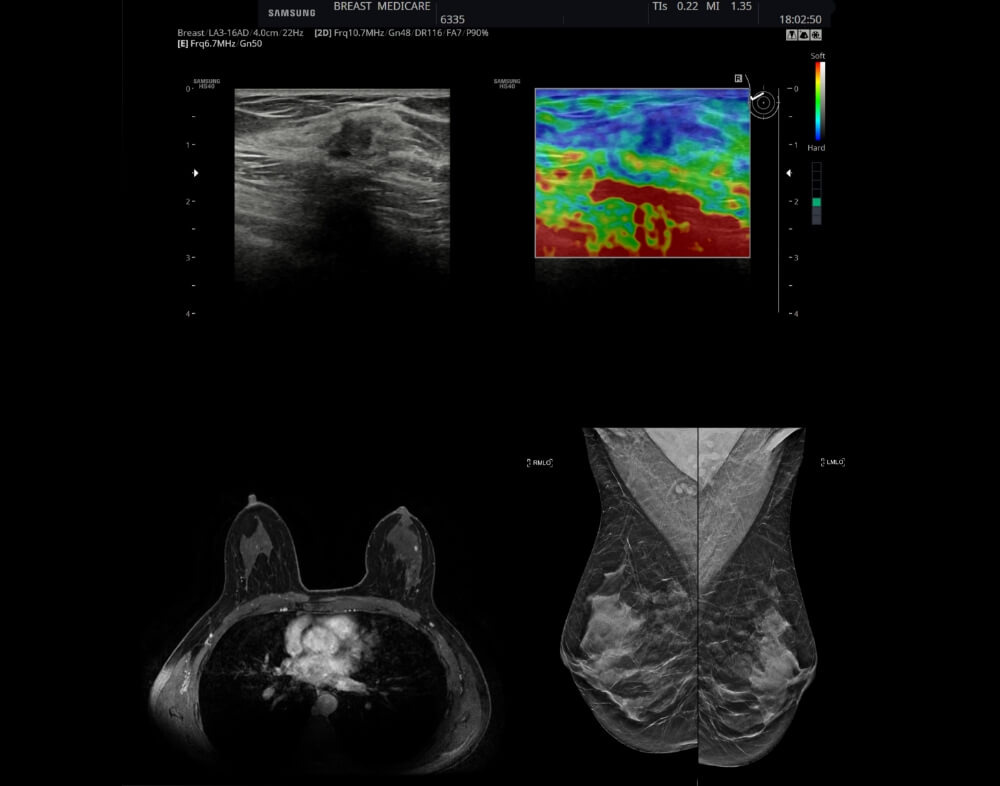

Η απεικονιστική διερεύνηση των μαστών περιλαμβάνει, ως βασικές εξετάσεις, την μαστογραφία και το υπερηχογράφημα.

Συχνά απαιτείται έλεγχος των μαστών και με μαγνητική τομογραφία. Η μαγνητική τομογραφία μας βοηθάει στην καλύτερη εκτίμηση του μεγέθους της βλάβης καθώς και στην ανίχνευση επιπλέον όγκων που δεν ανιχνεύθηκαν με τη μαστογραφία και το υπερηχογράφημα.

Είναι πολύ χρήσιμη σε γυναίκες με πυκνούς μαστούς, σε ορισμένους τύπους καρκίνου που εμφανίζονται συχνά με πολλές εστίες καθώς και όταν ο όγκος δεν είναι σαφώς ορατός στη μαστογραφία.